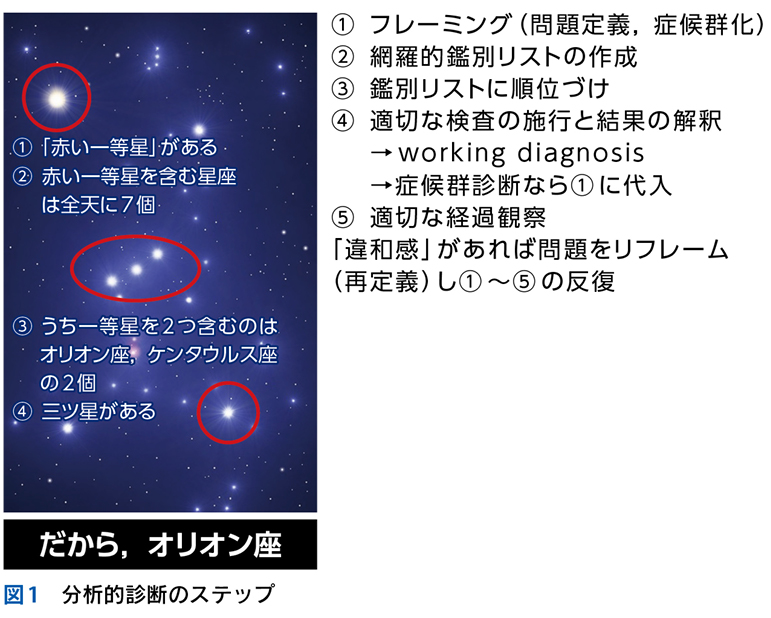

▶ 筆者の提唱する,分析的診断の「型」を図1に示した。冒頭に述べた「オリオン座を分析的に同定する手順」になぞらえ,診断推論を5つのステップにわけている。1つずつ解説しよう。

▶ また,ダイレクトに疾患の診断が行いにくい場合にはいったん「症候群名」で鑑別を挙げ,症候群診断を行い,診断された症候群を新たなフレームとしてその原因疾患の鑑別に移るという方法をとる。本章の最初に掲げた図1のステップ④で「症候群診断なら①に代入」とあるのはこのことである。